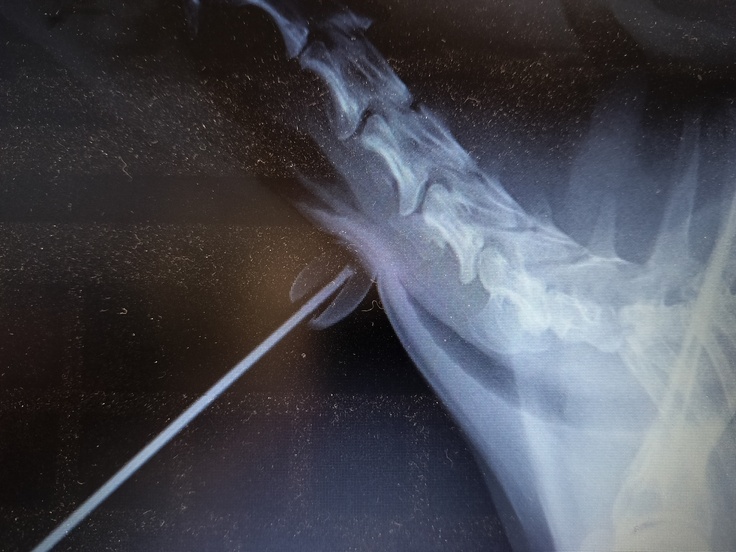

予想した以上に悪く色々な角度からレントゲンを撮っていただきましたが特に上を向いた状態で撮った写真はほとんど潰れていてこれでよく息ができるなと言われました。

もものレントゲン写真と気管虚脱の症状の説明書き、プロテーゼの実物画像になります。

こちらの画像は刺激を与えた時に 完全に 軟骨と気管接触していてふさがっているのがわかります。

下の方にUのようになっている部分がありますが上を向いた状態で撮影したそうですがこの状態だとステージⅣでほとんど潰れているそうです。